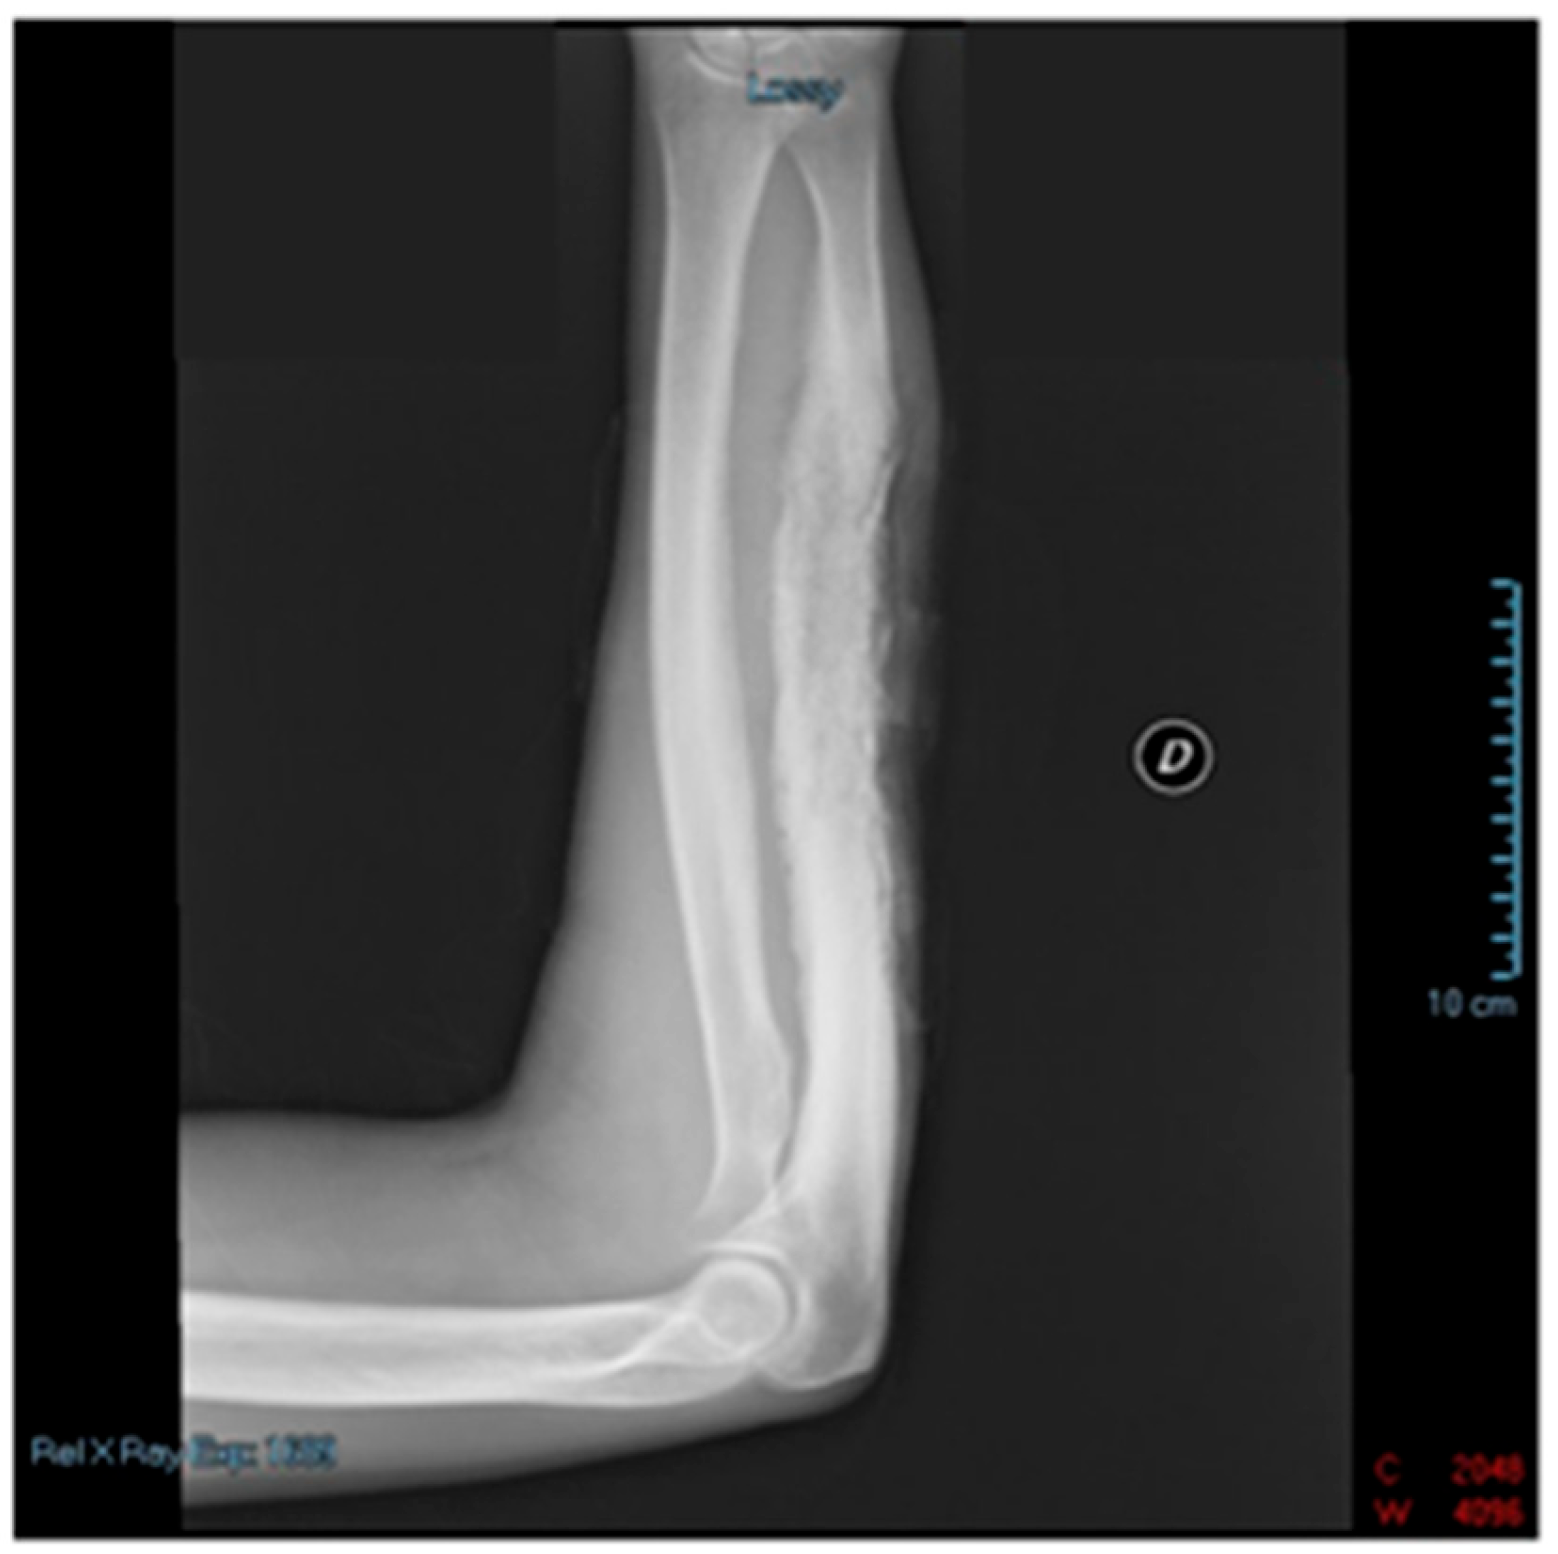

2. Case Report